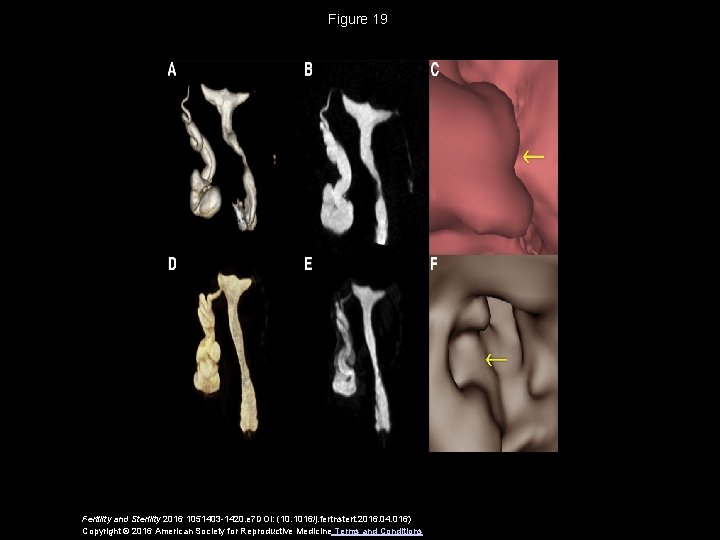

Figure 19 Fertility and Sterility 2016 1051403 -1420. e 7 DOI: (10. 1016/j. fertnstert. 2016. 04. 016) Copyright © 2016 American Society for Reproductive Medicine Terms and Conditions